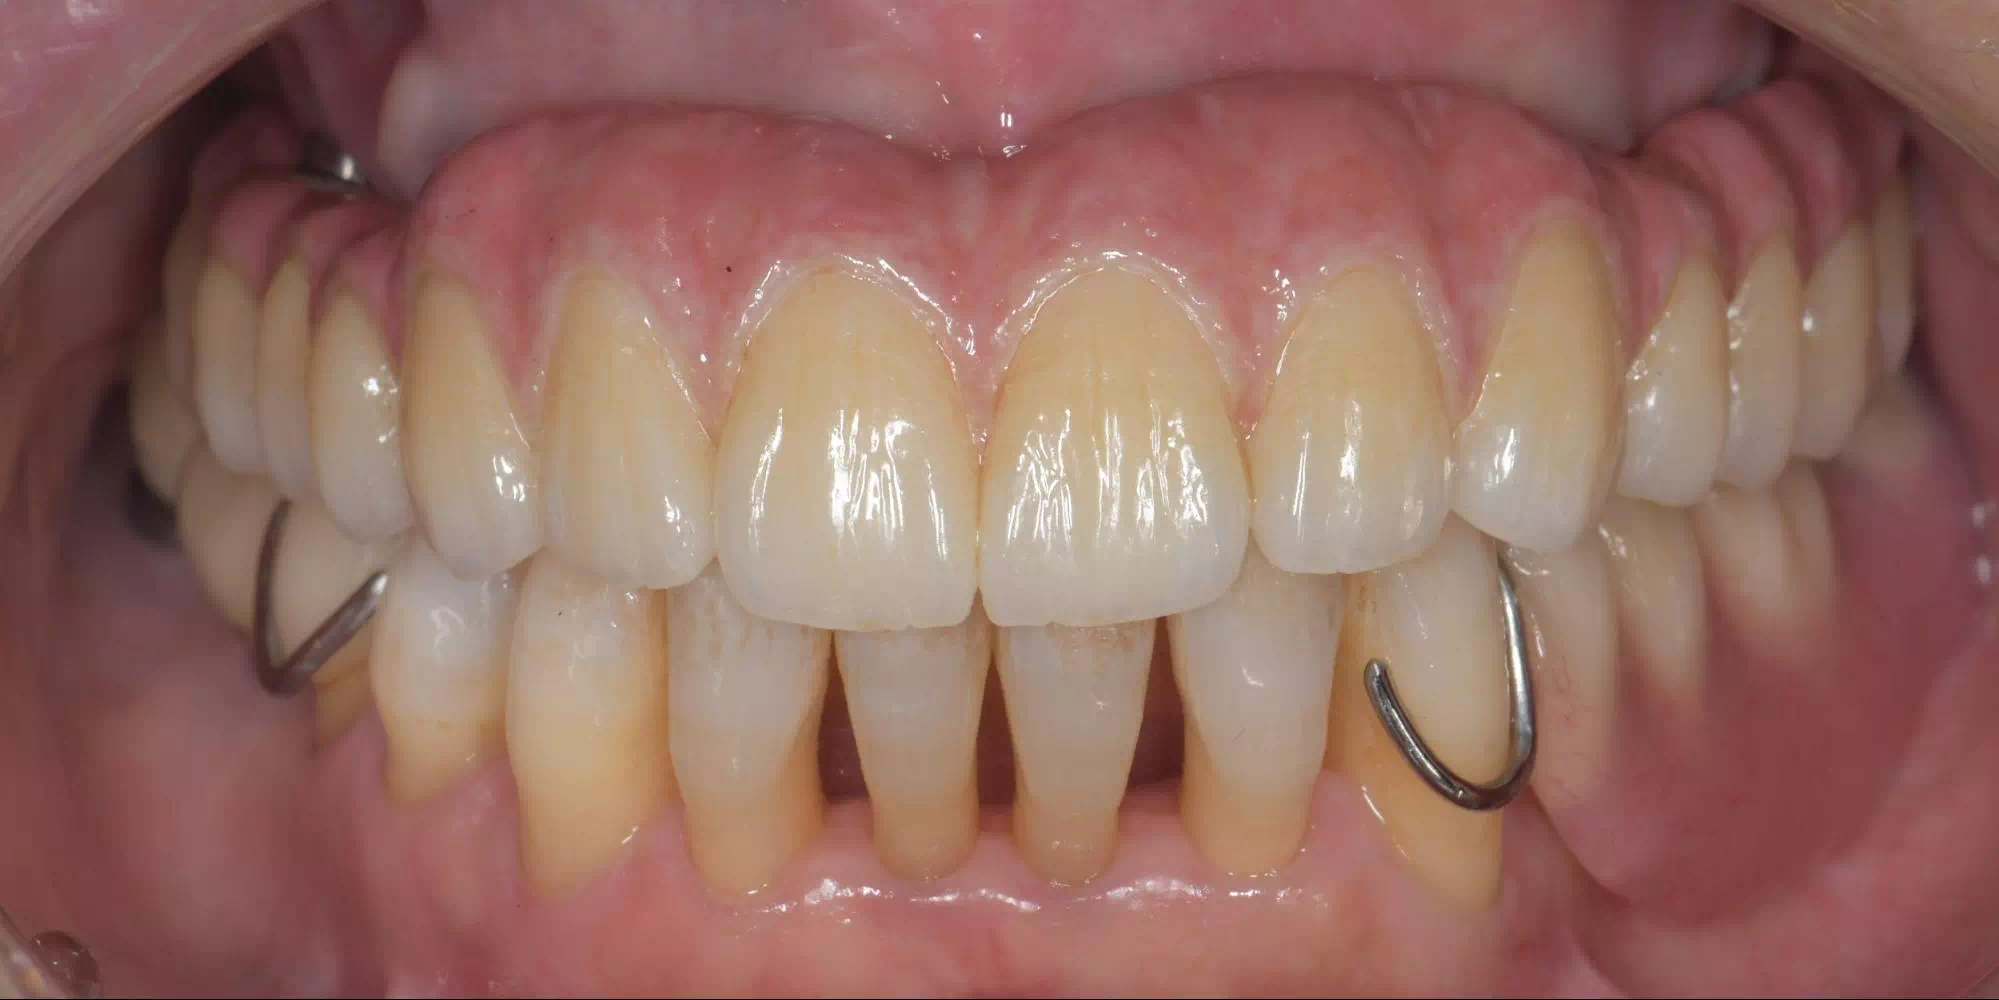

CASE HOME CASE 2025/10/21 抜歯即時埋入・即時荷重 症例 2025/10/21 GBR① 2025/10/21 インプラント 症例② 2025/10/21 インプラント 症例① 2025/10/21 矯正歯科 症例 2025/10/21 審美歯科 症例② 2025/10/21 審美歯科 症例① 2025/10/21 ガミースマイル 症例 2025/10/21 歯肉再生 症例② 2025/10/21 歯肉再生 症例① 2025/10/21 虫歯症例